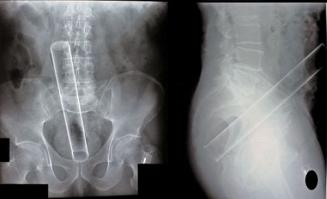

Необычные вещи, найденные в человеческом желудке (28 фото)

Ознакомьтесь с этими странными предметами, которые были найдены в человеческом кишечнике (которые, вероятно, заставили поёжиться даже самых опытных хирургов).